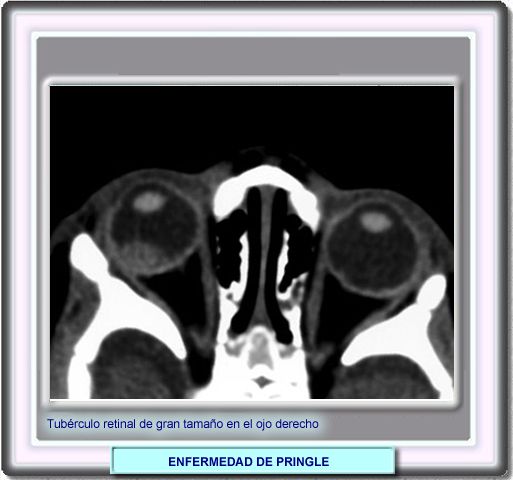

Facomas Otros hallazgos radiológicos son los tubérculos retinales, tumores benignos denominados facomas, que aparecen como masas blancas en la retina. Generalmente, no causan pérdida de la visión, pero pueden ayudar a definir el disgnóstico |